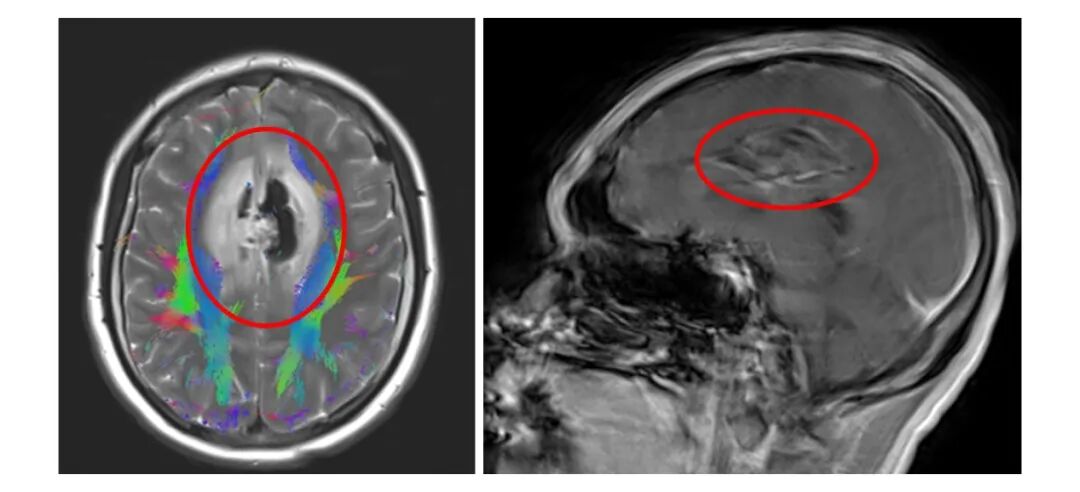

1月14日下午,东莞的怀孕32周的邓女士突然出现无法说话,四肢无力,并伴有低热,紧急送医后急查MRI平扫提示“双侧额叶及中线区占位性病变伴脑水肿、脑疝”。

画圈处为巨大脑肿瘤病变部位